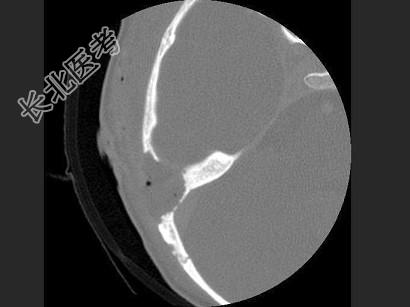

- 单项选择题女,17岁, 右耳乳突区隐痛,右耳后乳突区出现包块, 逐渐增大,CT检查如图, 最可能的诊断是 ( )

A、胆脂瘤

B、化脓性中耳炎

C、嗜酸性肉芽肿

D、中耳癌

E、听神经瘤